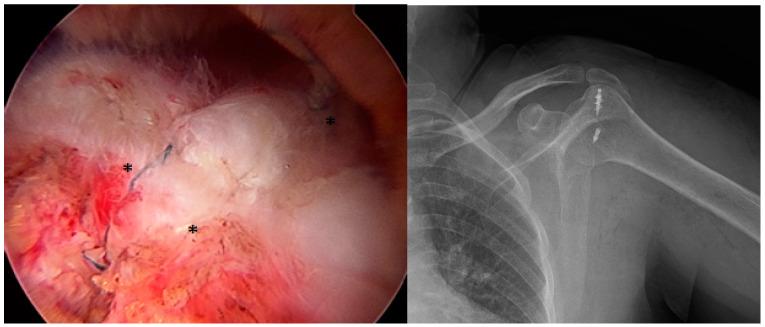

两种不同双排修复技术在关节镜下修复肩袖撕裂中的结果比较。

A Comparison of the Results of Two Different Double-Row Repair Techniques in Arthroscopic Repair of Rotator Cuff Tears.

肩部疼痛,主要涉及肩袖撕裂,是一种常见的肌肉骨骼疼痛类型,会严重影响生活质量。关节镜下肩袖修复已成为治疗有症状的全层肩袖撕裂的金标准。双排修复技术因其卓越的固定和愈合效果而被广泛应用。然而,减少植入物数量可能会降低治疗成本,并引发对其对临床结果和再撕裂率影响的质疑。本研究比较了两种类似经骨双排修复技术的功能结果和再撕裂率:一个锚钉和一个推锁(第1组),以及两个锚钉和两个推锁(第2组)。

对53例接受关节镜修复新月形肩袖撕裂(3 - 5厘米)的患者进行了一项前瞻性、随机、单盲研究。在手术前和手术后24个月,使用Constant-Murley评分和肩部外展角度对患者的肩部功能进行评估。使用MRI评估再撕裂率。

两组患者术后Constant评分均有显著改善(第1组:84.1;第2组:84.0;P>0.05)。第1组的再撕裂率(23.1%)略高于第2组(18.5%),但差异无统计学意义(P>0.05)。两组间肩部外展角度改善情况相似,结果无显著差异。尽管双锚钉技术成本更高、手术时间更长,但提供了更稳定的固定,但其功能结果与单锚钉方法相当。

在双排修复中使用较少的植入物可提供相当的功能结果和再撕裂率,并为外科医生提供了一种经济有效的选择,尤其是在他们学习曲线的初期。然而,在需要改善机械稳定性的情况下,双锚钉技术可能更有益。这些发现为平衡肩袖修复中的成本和有效性提供了有价值的信息。